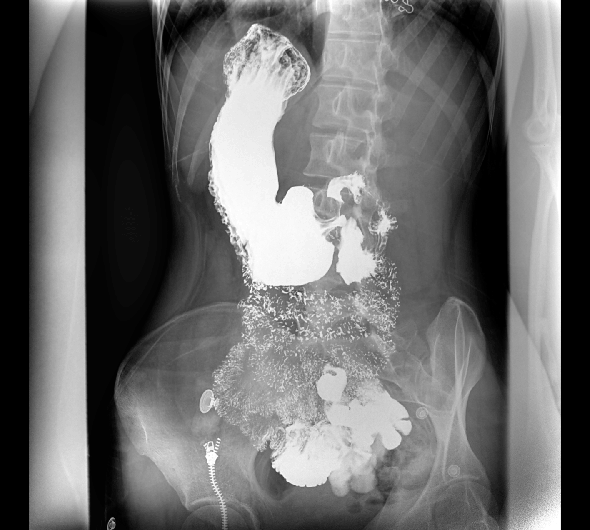

臨床圖像